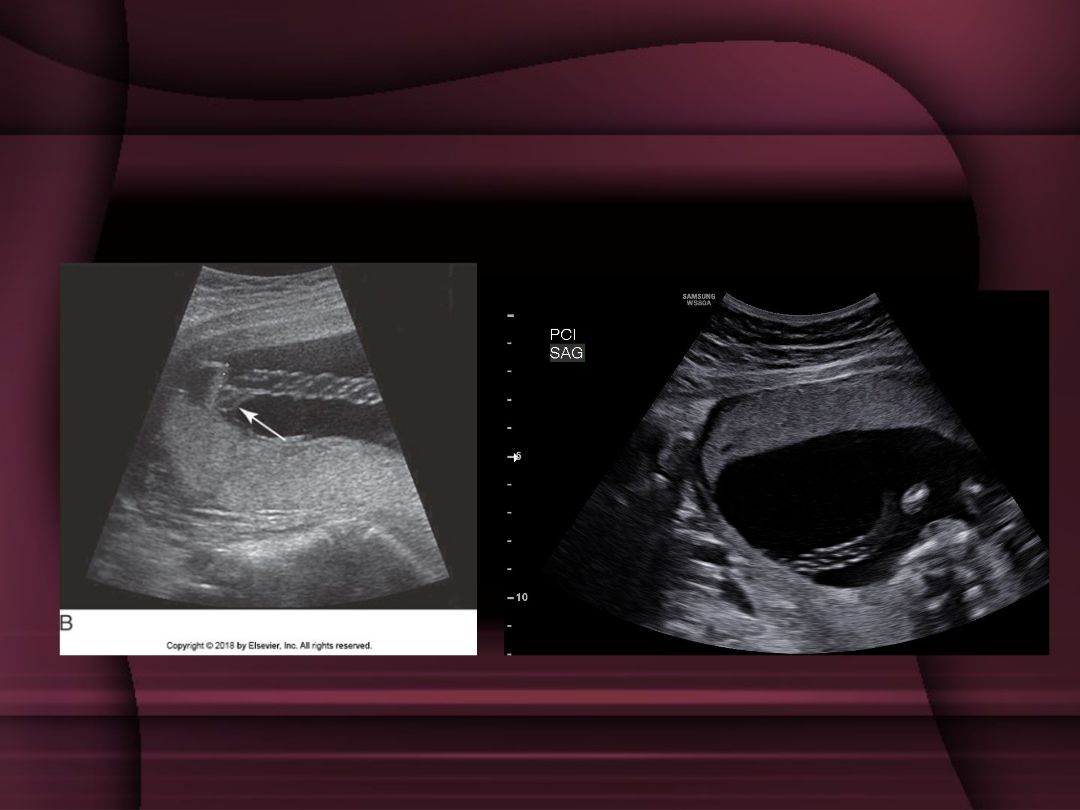

6-8. A 28-year-old G4P2 at 20 weeks' gestation presents for her fetal anatomical survey. There have been no pregnancy complications to date. The placenta is imaged with the findings shown below. What do you document on the ultrasound report?

Posterior placenta

Posterior placenta with chorioangioma

Posterior placenta with succenturiate lobe

Posterior placenta with remote subchorionic hematoma